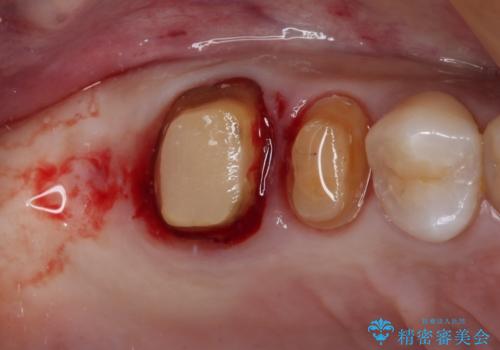

不安定な咬み合わせとなっており、クラウンの表面が剥離していたため、インプラントによる欠損補綴治療を行い、手前2つの歯も一緒に補綴治療を行うこととしました。

治療中の仮歯も頻繁に壊れておりましたが、インプラントの土台が歯肉上に出てからは咬み合わせが安定し、仮歯が壊れることもなくなりました。